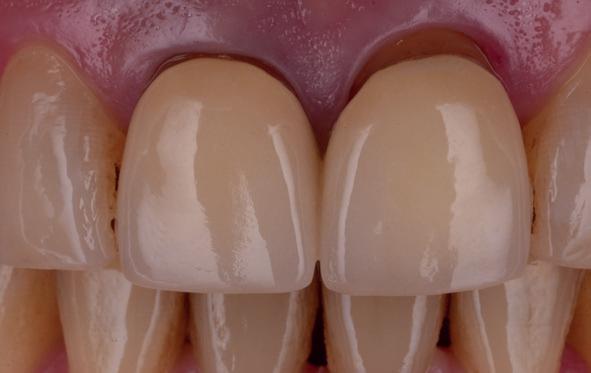

Esthetiek in de tandheelkunde, met name in het front, is een samenspel tussen de roze zachte weefsels en de witte harde weefsels. In het Engels wordt dit ook wel aangeduid met “pink and white esthetics”, waarbij het verkrijgen van correcte pink esthetics over het algemeen een grotere uitdaging vormt dan de white esthetics. Deze roze esthetiek is vooral van belang bij gebitselementen waarbij sprake is van recessie (het terugtrekken van de gingivalijn, waardoor de radix en een langere tand zichtbaar worden). De situatie wordt nog uitdagender wanneer een tand of kies niet is aangelegd, of in het verleden is verwijderd. Het element zorgt er immers voor dat de gingiva rondom de natuurlijke kroon ligt en dat er voldoende weefseldikte rondom deze kroon aanwezig is. Als het element ontbreekt, groeit het alveolaire bot dicht, omdat er geen radix meer is, en daarmee ook de mucosa (wanneer er geen element meer aanwezig is, spreken we niet meer van gingiva maar van mucosa), die dan afgevlakt is. De papillen tussen de afwezige elementen vlakken dan ook af.

Om één of meer afwezige elementen te herstellen bij een vaste voorziening, kan er een etsbrug of kunnen er implantaten worden geplaatst. De esthetiek valt of staat hierbij met de aanvulling van de zachte weefsels, zowel in de vorm van verbreding hiervan als het creëren van een zogenoemd emergence profile –dat wil zeggen dat de tand op een natuurlijk ogende wijze vanuit het tandvlees tevoorschijn moet komen.

tinaal geslepen te worden als er geen 1,5 mm ruimte voor de vleugels behaald kan worden. De ruimte was op de dunste plekken 1 mm, dus een kleine preparatie in de 12 en 22 palatinaal was nodig. Omdat de kaak volledig afgevlakt was en dun was geworden, kunnen de dummies van de etsbrug enkel op de kaak “gelegd worden”, maar daarbij zijn er geen papillen en staat de cervicale rand van de dummies net voor de kaak. Een esthetisch resultaat kan daarmee niet behaald worden. Daarom is een aanvulling van de zachte weefsels in de breedte nodig, als het creëren van een emergence profile, waarbij het oogst alsof de gebitselementen uit het weefsel vertrekken.

Voor de aanvulling zachte weefsels chirurgie werd gekozen voor de VISTA techniek, hierbij worden er twee incisies partial thickness flap hoog in de mucosa gemaakt, waarna er ruimte vanuit de incisies wordt getunneld tussen de gingiva en het periost door middel van VISTA tunnel instrumenten. Uit het palatum links werd een vrij gingivatransplantaat geoogst van 15x10 mm met een dikte van 3 mm, die voor inhechten werd geëpithelialiseerd. Als het epitheel niet wordt verwijderd, kan deze graft door

pincisies met hechtingen naar het buccale en coronale deel getrokken en aldaar ingehecht. Met twee incisies werd ook de emergence profile gecreëerd (afbeelding 6-13). Voor een goede genezing van het

18. Etsbrug frontbeeld